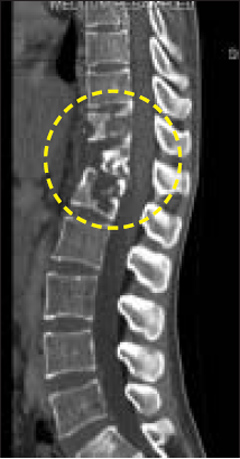

척추결핵 환자의 영상사진. 원 안이 결핵 감염 부위./강남세브란스병원 제공

척추결핵이란 결핵균이 척추에 감염돼 생기는 질환이다. 결핵균은 보통 호흡기를 통해 몸으로 들어와 폐에서 증상을 일으키지만(폐결핵), 이 균이 혈액·림프액을 따라 척추로 옮겨가면 허리 통증을 유발한다(척추결핵). 전체 결핵 환자의 10~15%가 폐가 아닌 다른 곳에 결핵균이 감염되는데, 그 중 절반은 척추결핵이다. 이렇듯 결핵균이 척추로 잘 이동하는 이유는 척추 주변에 혈관이 많이 분포돼 있기 때문이다.

척추결핵이 생기면 초기에는 미열·식은땀·식욕부진과 같은 몸살 기운이 나타난다. 그러다가 척추에 염증이 생기면서 허리 통증까지 겪는다. 강남세브란스병원 신경외과 김근수 교수는 "몸살 기운이 있으면서 허리를 굽혔다 펼 때 통증이 느껴진다면 척추결핵을 의심해볼 수 있다"며 "이때는 폐결핵과 달리 신경외과나 정형외과에서 진료를 받아야 하며, 흉부 엑스레이 대신 MRI·CT(컴퓨터단층촬영)나 혈액검사를 받아봐야 한다"고 말했다.